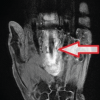

The patient had a right-hand carpal tunnel release and a 4th and 5th trigger finger release done 9 months prior at an outside hospital. She was approximately 2 months into her post-operative physical therapy when she first noticed swan necking off her 4th digit. She presented to her original surgeon at the outside medical center, who recommended continued observation. She subsequently completed her physical therapy and was given a metal double-ring splint, which she wore for approximately 2 weeks before discarding. She presented to our facility 9 months after the initial surgery as a referral from her primary care physician. She denied any numbness, tingling, or weakness at that time. Her medical history included a history of deep vein thrombosis. Her past surgical history included bilateral carpal tunnel release, open reduction internal fixation of a left distal radius fracture, as well as radical tenosynovectomy and first compartment release of the right first dorsal compartment. The patient stated that she drank alcohol occasionally but denied any history of smoking or drug use. Physical examination revealed a right-hand swan-neck deformity of the 4th digit with 5° of flexion contracture of the MCP joint, 10° extension at the PIP, and 5–10° of flexion contracture at the DIP joint. These findings were all passively correctable, and pressure of the A2 pulley region also passively corrected the deformity. In addition, the patient was able to flex and extend the digit actively. However, the patient could not make a full fist and had a tip-to-palm distance of approximately 1 cm of the ring finger. Due to the previous A1 pulley release, our suspicion was raised for possible extension into the A2 pulley. Therefore, an MRI was ordered to evaluate further. The MRI results revealed that the A2 pulley had been disrupted, with bowstringing of the flexor tendons and an increase in the distance between the flexor tendons and the proximal phalanx and metacarpal. The resulting flexion of the MCP resulted in a stepwise progression to SND of the right 4th finger with no acute fracture or dislocation (Fig. 3).

The 4th finger flexor and extensor tendons were intact; however, the flexor tendons were slightly separated from the proximal phalanx and metacarpophalangeal joint. This interesting finding appeared to be bowstringing at the proximal phalanx.